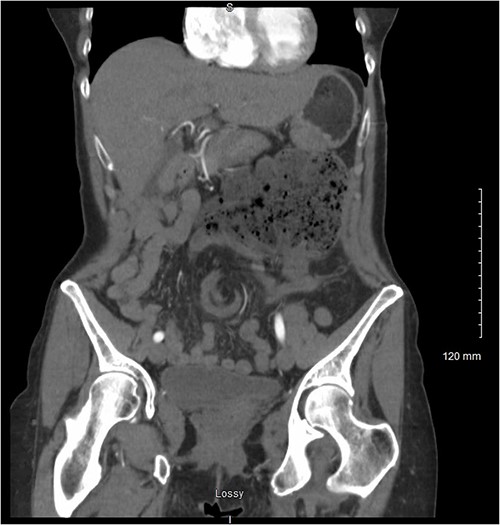

Her persistent pain prompted her to seek further care via the emergency department where computerised tomography (CT) of the abdomen and pelvis revealed concern for congenital malrotation with closed-loop bowel obstruction secondary to intestinal volvulus of the cecum and ascending colon (Fig. 1). At this time, vital signs were found to be within normal limits. White blood cell count was found to be 7.9 and lactate was slightly elevated at 2.6. Her abdomen was tender in the left upper quadrant, with a palpable fullness underlying the area of maximum tenderness. She did not have peritoneal signs on abdominal exam. Based on these findings, the decision was made to proceed to the operating room for exploratory laparotomy.

Coronal view of the patient’s CT abdomen and pelvis showing a central mesenteric swirl and adjacent fecalised bowel concerning for volvulus.